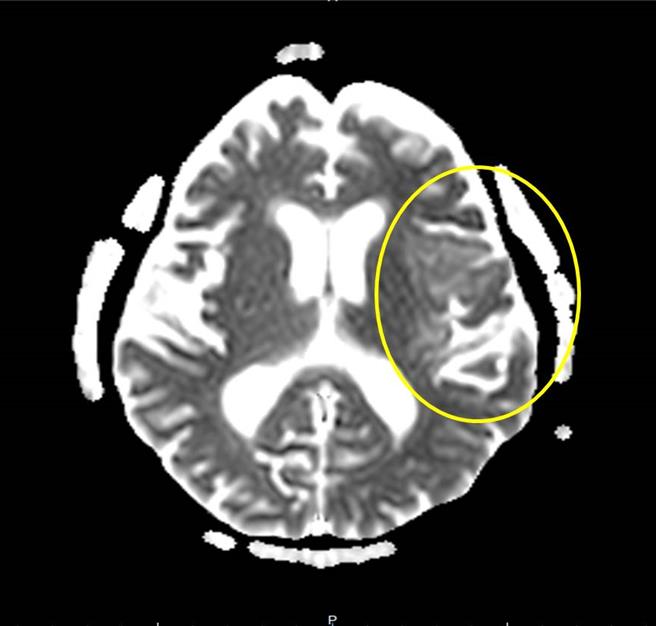

醫師也為婦人安排腦部核磁共振檢查,結果診斷為腦炎及腰椎穿刺檢查採集腦脊髓液送檢驗,檢驗結果為第一型單純皰疹病毒感染,會同感染科主任黃駟榮使用抗病毒藥物治療,治療後病人從意識昏迷、無法溝通,恢復到可以做簡單溝通。

衛生福利部豐原醫院感染科主任黃駟榮表示,腦炎病因有病毒、細菌、真菌、寄生蟲等,病毒占大多數,而單純疱疹病毒又占病毒性腦炎的多數,在免疫力較差的情況下,原本發生在身體其他部位的病毒感染,可能經由血液將病毒擴散至腦部而引發腦炎,如治療不及時會造成死亡率高,存活後易有神經相關後遺症,例如意識不清、癲癇、實質性的腦部損傷等。